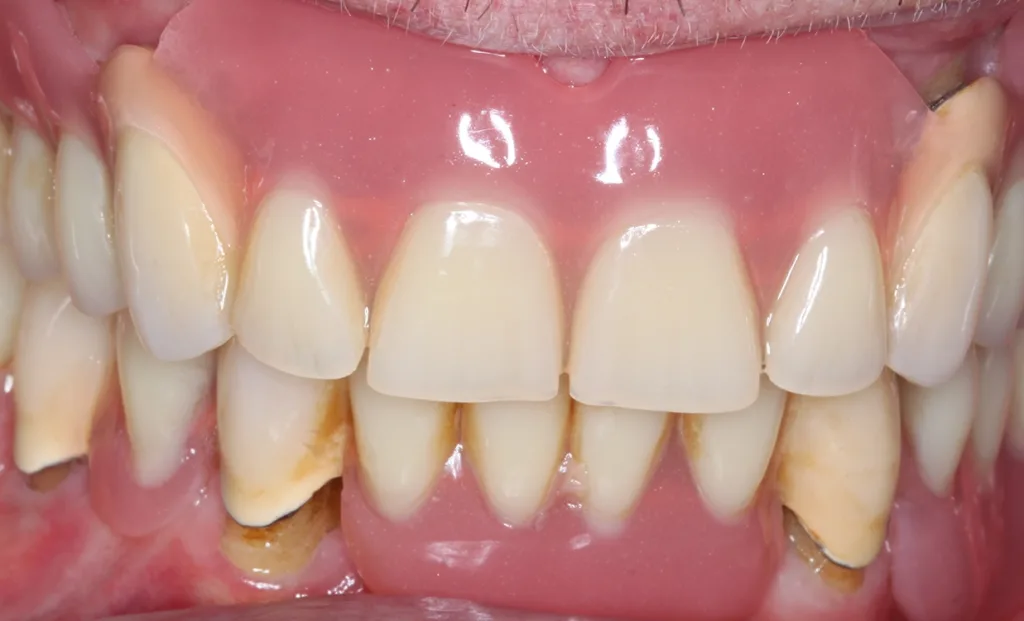

Abb. 3 a–e: Klinische Dokumentation eines 63-jahrigen männlichen Patienten (geb. 05.09.1961). Die Fotodokumentation erfolgte erst am Tag der AIT und nicht im Rahmen der klinischen und radiologischen und 47 wurden vor der AIT entfernt. An den Zahnen 13 und 23 war neben der peniblen subgingivalen Instrumentierung die Applikation von Straumann® Emdogain® (Straumann Group, Basel, Schweiz) vorgesehen.Walter

Abb. 3 a–e: Klinische Dokumentation eines 63-jahrigen männlichen Patienten (geb. 05.09.1961). Die Fotodokumentation erfolgte erst am Tag der AIT und nicht im Rahmen der klinischen und radiologischen und 47 wurden vor der AIT entfernt. An den Zahnen 13 und 23 war neben der peniblen subgingivalen Instrumentierung die Applikation von Straumann® Emdogain® (Straumann Group, Basel, Schweiz) vorgesehen.

Es handelt sich hierbei um einen 63-jährigen männlichen Patienten (geb. 05.09.1961). Allgemeinmedizinisch war eine rheumatoide Erkrankung und die Einnahme von Methotrexat (Folsäureantagonist, Zytostatikum und Immunsuppressivum) dokumentiert. Etwaige orale Nebenwirkungen dieser Medikation lagen nicht vor. Herr B. war Nichtraucher. Der Patient wünschte maximalen Zahnerhalt und wurde daher zur parodontalen Therapie der bereits weit fortgeschrittenen Parodontitis an eine spezialisierte Praxis überwiesen. Zu diesem Zeitpunkt waren im Oberkiefer noch 2 und im Unterkiefer noch 5 Zähne vorhanden.

Der parodontale Screening-Index (PSI) an den verbliebenen Zähnen zeigte erhöhte Zahnlockerungen, stark entzündete und blutende Areale sowie Sondierungstiefen weit über 5 mm hinaus. Es lag dem zufolge ein Code 4* und damit die Notwendigkeit gründlicher Diagnostik vor. Die weiterführenden parodontalen Untersuchungen führten zur Diagnose einer generalisierten Parodontitis Stadium IV Grad C [46]. Die parodontal entzündete Wundfläche betrug 1088,69 mm2 [47]. Radiologisch konnten neben dem generalisierten horizontalen Knochenverlust auch ausgeprägte vertikale Defekte z.B. an den Zähnen 13 und 23 detektiert werden. Darüber hinaus wurde ein Chairside Vitamin-D-Test durchgeführt (Botiss, Straumann Group, Basel, Schweiz). Der Wert betrug 10 ng/ml und bedeutete, dass hier ein schwerer Vitamin-D-Mangel mit entsprechenden Implikationen für den Knochenstoffwechsel vorlag. Dem Patienten wurde eine Vitamin-D-Supplementierung mit zunächst 2000 IE und die Vorstellung bei seinem Hausarzt zu etwaiger weiterer Diagnostik und Festlegung einer optimierten Vitamin-D-Nahrungsergänzung empfohlen [48].